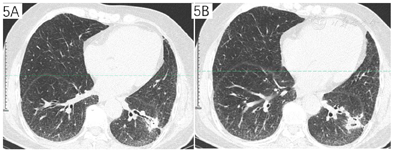

分别于2021年12月30日、2022年1月6日、2022年1月17日、2022年1月25日行4次支气管镜检查及治疗,超声探查示左下叶前基底段外侧支异常低回声,局部予乙酰半胱氨酸+生理盐水反复灌洗后,注射猪源纤维蛋白粘合剂+两性霉素B,术后咳嗽症状缓解出院。2022年3月11日于我院通州院区住院,3月12日胸部CT平扫(经支气管镜局部注药后复查),曲菌球较我院初诊缩小(图2)。于2022年3月21日行经皮穿刺注药(猪源纤维蛋白+两性霉素B),复查即刻CT示气胸,予胸腔闭式引流(图3)。2022年3月23日行微波消融治疗(图4),45 W消融3 min,复查CT示覆盖病灶,继续保留闭式引流,次日复查胸片无气胸,拔除引流管。

患者复查胸部CT示病灶较前缩小(图5)。

四、曲霉菌属能在50℃生长,温度超过70℃时会死亡[8]。故热消融技术为可能的根治性治疗手段。目前仅有1例射频消融治疗肺曲菌球的报道[9],经术后2次穿刺活检均显示有曲霉菌丝,但培养阴性,且在33个月的随访过程中腔内空洞消失,显示为瘢痕样组织。但是热消融,包括射频消融及微波消融本身,均可能会引起空腔,空腔时肺曲菌球形成的危险因素[10,11,12,13]。目前消融技术应用于肺曲菌球治疗领域尚未有更充分的数据,未检索到微波消融治疗的案例报道。微波消融区域温度可控制在70℃以上,满足灭活曲霉菌的条件,理论上可选用。鉴于无既往经验可参照,空洞形成本身又是曲菌球形成的危险因素,故选用较为保守的参数,45W持续3min,病灶覆盖满意,目前消融术后随访近3月,提示病灶已明显缩小,无继发空洞形成。